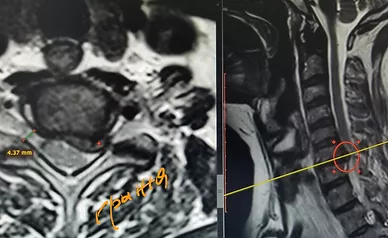

Микрохирургическое удаление грыжи шейного отдела позвоночника с межтеловой фиксацией

Микрохирургическое удаление шейной грыжи - это операция, проводимая на шейном отделе позвоночника для удаления межпозвоночной грыжи, остеофитов.

Задачами операции являются прекращение сдавления спинного мозга, корешков спинного мозга, а также позвоночных артерий грыжей, остеофитами и гипертрофированными связками.

Как правило такая операция заканчивается установкой межтелового кейджа (имплантата) на месте удаленного диска, что позволяет создать условия для возникновения межтелового блока, восстановить изначальную высоту межтелового промежутка, межпозвонковых отверстий и физиологического лордоза.

Операция показывает высокую эффективность при преобладании боли в руке над болью в шее с наличием четкого субстрата на МРТ-снимках, соответствующего клинико-неврологической симптоматике.